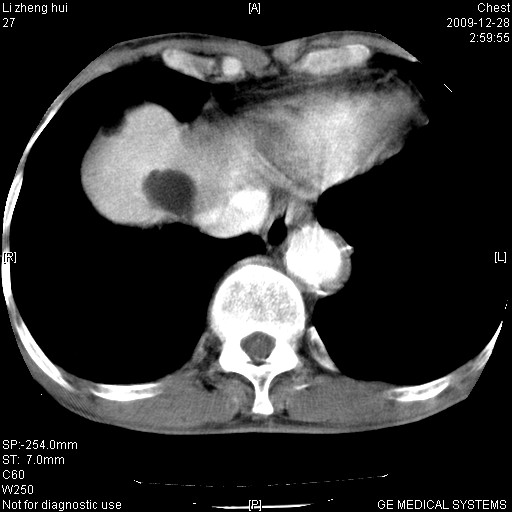

男  79岁 胸部痛急诊入院,晚上做的增强

考虑主动脉瘤?(增粗、钙化、壁血栓?)

动脉瘤伴附壁血栓

1)考虑胸主动脉壁间血肿或夹层动脉瘤。2)多发性肝囊肿。

1)考虑胸主动脉附壁血栓或夹层动脉瘤。2)多发性肝囊肿。